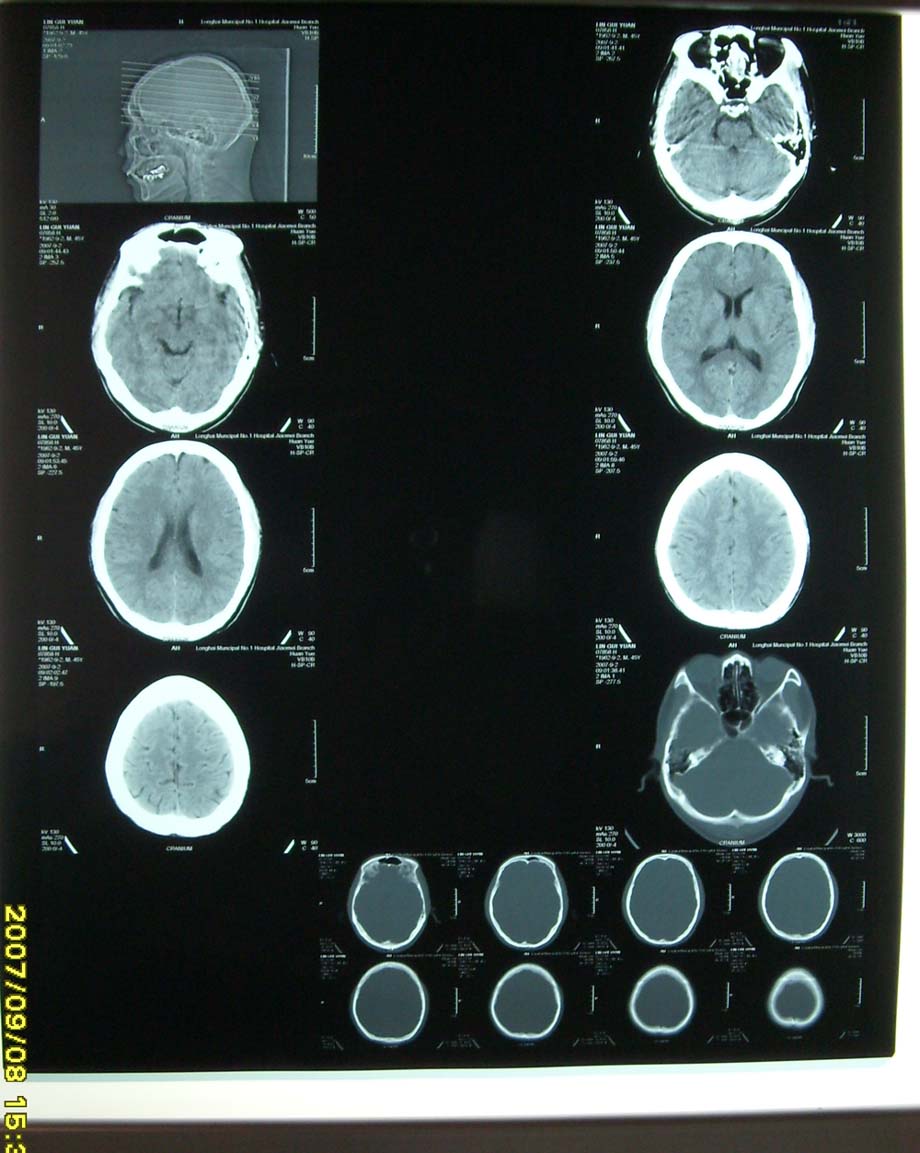

我医院使用的是西门子欢悦单排螺旋ct,打印机是柯达8150,为什么有时打印出来的图片是这样,再请问一个问题:为什么胶片盒还剩一张或二张胶片,而电脑屏幕却提示没有胶片呢,这样每次都要浪费一、二张胶片,有什么好办法能解决这个问题.请指教。